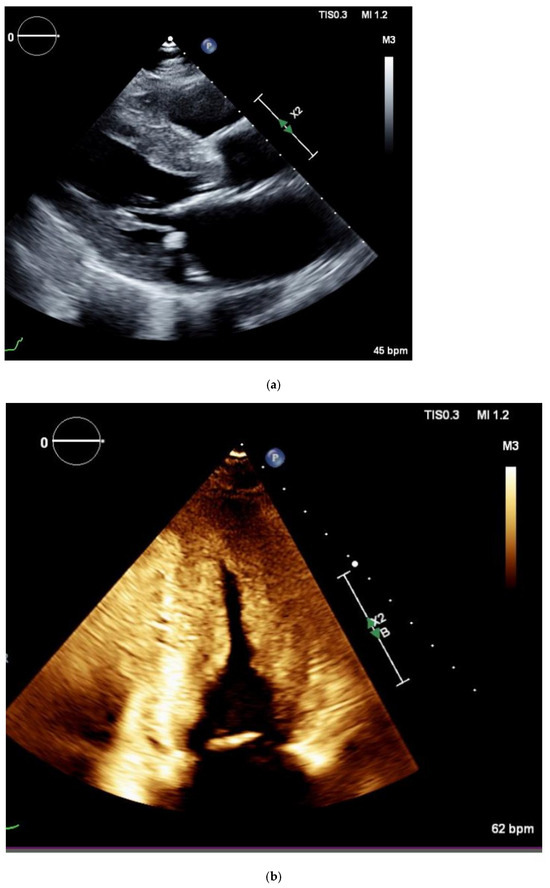

- Polo, J.M.; Barrenechea, A.R.U.; Martí, P.R.; Pérez-Palacios, R.; Gutiérrez, A.G.; Juana, E.B.; Gracia, A.A.; Ayala, S.A.; Arregui, M.Á.A. Echocardiographic markers of cardiac amyloidosis in patients with heart failure and left ventricular hypertrophy. Cardiol. J. 2023, 30, 266–275. [Google Scholar] [CrossRef]

- Luis, S.A.; Pellikka, P.A. Is speckle tracking imaging ready for prime time in current echo clinical practice? Prog. Cardiovasc. Dis. 2018, 61, 437–445. [Google Scholar] [CrossRef] [PubMed]

- Phelon, D.; Collier, P.; Thavendiranathan, P.; Popović, Z.B.; Hanna, M.; Plana, J.C.; Marwick, T.H.; Thomas, J.D. Relative apical sparing of longitudinal strain using two-dimensional speckle-tracking echocardiography is both sensitive and specific for the diagnosis of cardiac amyloidosis. Heart 2012, 19, 1442–1448. [Google Scholar] [CrossRef]

- Leitman, M.; Tyomkin, V. Apical Sparing in Routine Echocardiography: Occurrence and Clinical Significance. J. Cardiovasc. Dev. Dis. 2024, 11, 262. [Google Scholar] [CrossRef]

- Pagourelias, E.D.; Mirea, O.; Duchenne, J.; Van Cleemput, J.; Delforge, M.; Bogaert, J.; Kuznetsova, T.; Voigt, J.-U. Echo Parameters for Differential Diagnosis in Cardiac Amyloidosis: A Head-to-Head Comparison of Deformation and Nondeformation Parameters. Circ. Cardiovasc. Imaging 2017, 10, e005588. [Google Scholar] [CrossRef]